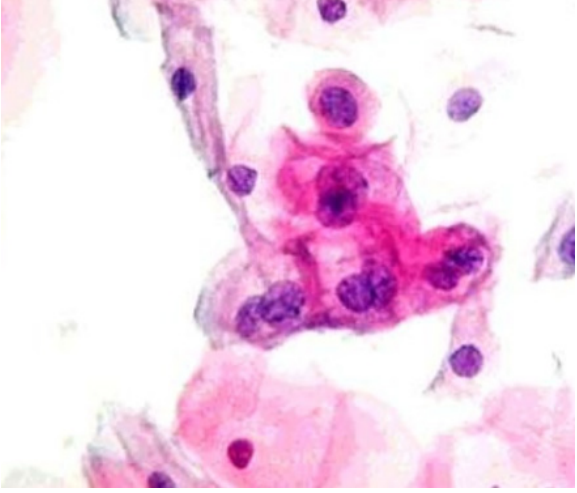

É o exame do colo do útero com um microscópio (colposcópio) após a aplicação de reagentes para realçar áreas suspeitas.

- Aplicação de Ácido Acético (3-5%): Coagula as proteínas. Células com alta atividade de replicação (lesões) ficam com um aspecto branco (epitélio acetobranco).

- Teste de Schiller (Aplicação de Lugol): O iodo cora o glicogênio das células normais de marrom. Células displásicas, pobres em glicogênio, não se coram e ficam amareladas (iodo-negativas ou Schiller-positivo), indicando o local ideal para a biópsia.

- Grau 1 (Menores): Compatíveis com ASC-US/LSIL. Incluem epitélio acetobranco tênue, borda irregular e mosaico ou pontilhado fino.

- Grau 2 (Maiores): Sugerem lesões de alto grau. Incluem epitélio acetobranco denso, mosaico grosseiro e atipia vascular.